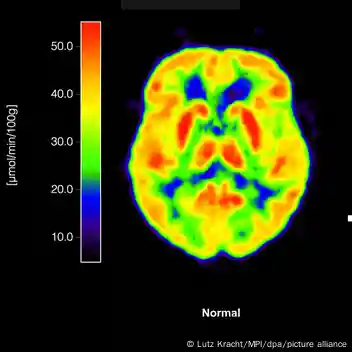

الزائمر کی بیماری بین الاقوامی سطح پر ڈیمنشیا کے مرض کی سب سے عام وجہ ہے اور اس کا تعلق پروٹینز کی ان دو مخصوص لیکن کلیدی اقسام سے ہے، جو دماغ میں پائی جاتی ہیں۔

ان میں سے ایک پروٹین کا نام ایمی لوئڈ (amyloid) ہے جبکہ دوسری ٹاؤ (tau) کہلاتی ہے۔ برطانیہ میں کیے جانے والے بلڈ ٹیسٹ تجربات میں ماہرین کی توجہ ٹاؤ نامی پروٹین کی ایک خاص ذیلی قسم 'پی ٹاؤ 217‘ پر مرکوز رہے گی۔